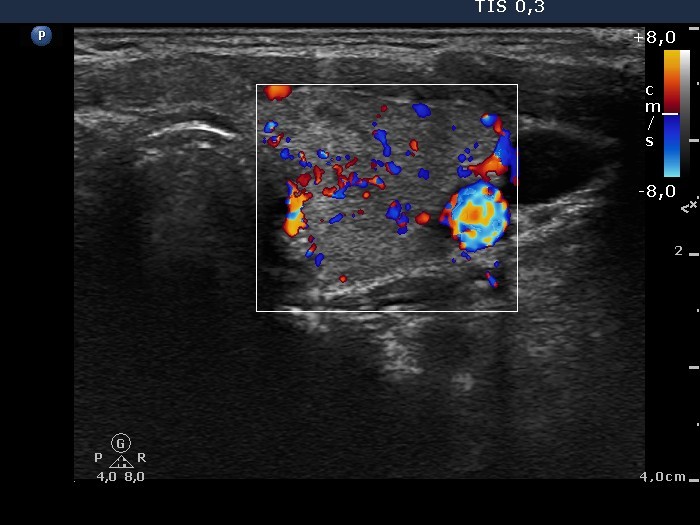

Graves' disease - Case 1049

Follow-up investigation 33 months after first visit (ultrasonographic picture 6)

Patient on daily 20 mg methimazole therapy in euthyroid state

Left lobe, transverse scan, color Doppler mode. The vascularization is average.